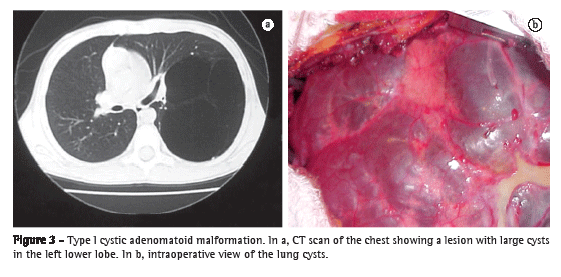

The lesions vary widely in size and can affect an entire lobe or part of it, as well as an entire lung. The lesion can affect both sides of patients with equal frequency and can affect any lung lobe, although it occurs more frequently in the lower lobes and rarely affects more than one lobe (85-95% in only one lobe; Figure 3), being slightly more common in males than in females.(4,15,32) Although CCAM is connected with the tracheobronchial tree and derives its blood supply from the pulmonary circulation, the affected lung area shows reduced vascularization.(15) The incidence of CCAM is approximately 1 case per 10,000-35,000 pregnancies,(4,15,37,38) and CCAM has not been associated with race, age, maternal exposure to any given factor, or genetic factors.(32)

Type I CCAM (Figure 3) is characterized by a lung mass, generally confined to a lobe, containing a single cyst or multiple cysts over 2 cm (3-10 cm) in diameter,(5,15,27,32,39) covered by pseudostratified ciliated epithelium, with areas of mucus-secreting epithelium covered by fibromuscular tissue,(5,15,27,32,39) and generally filled with air or mucus. This type of lesion results from injury during the canalicular or pseudoglandular period of lung development.(32) The adjacent lung tissue is normal and is generally compressed by the malformation, which has the effect of an intrathoracic mass(15,35) and can lead to respiratory failure in the neonatal period. Patients with type I CCAM generally present with symptoms in the first week of life. In extremely rare cases, type I CCAM patients can remain asymptomatic into adulthood. The combination of type I CCAM and other malformations is also rare.(15)